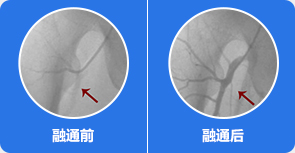

2血管疏通,解决血管供血问题

借助国家专利技术可视血堵融通术,打通股骨头血管管内各种类型淤堵损伤,解决血管供血问题,恢复股骨头血供。

治疗前:通过影像,可知道股骨头周边血管分布、病灶部位,血管哪里堵塞清晰可见

治疗中:旋股内侧动脉中的血脂、血栓逐渐被疏通

治疗后:通过融通术,旋股内侧动脉逐渐恢复血供,骨关节周围血流量加快,骨细胞供血恢复正常